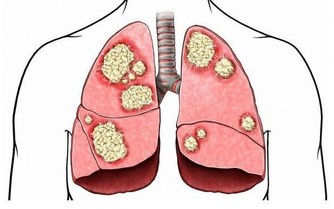

我們知道,腎臟的一個主要功能就是排水,尿液就是從這裡產生的,

一旦腎臟的排水功能出現了問題,喝水的時候就需要注意一些了。

為什麼呢?因為喝了很多水,但不能及時排出去的話,會形成水腫,甚至會加重病情。

哪些腎病患者需要控制飲水呢?是那些腎臟排水功能受損的患者。

臨床上認為,“少尿”的標準是每天少於400ml,

“無尿”的標準是每天少於100ml,這些腎病患者是需要控制飲水的。